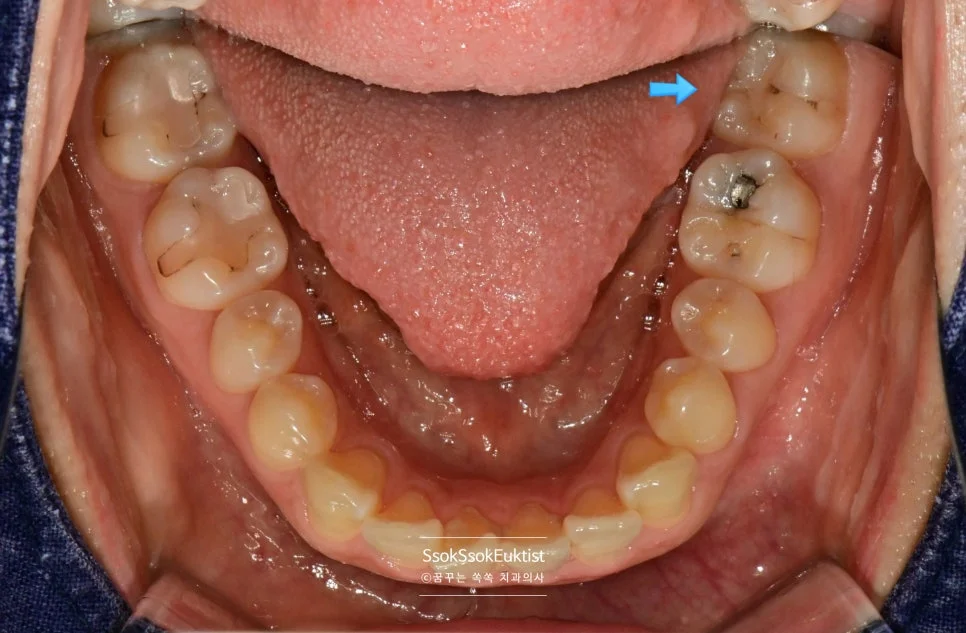

왼쪽 아래 사랑니가 앞 치아에 걸리지 않고 잘 올라왔는데 그만 뒤쪽에 턱뼈에 걸려버렸네요. 이런 경우 사랑니가 턱뼈의 잇몸에 의해 덮여있게 되고 만성적인 염증 상태가 되게 마련입니다.

이 또한 뒤쪽에 턱뼈에 걸리지 않게 길만 만들어주면 쉽게 발치할 수 있는 치아입니다.

맹출 중에 통증을 호소한 사랑니

사랑니를 제거하기 위해서 잇몸의 절개가 필요하고, 매복 방향과 정도에 따라 치조골 혹은 사랑니를 분리하여 빼야 하는 경우인데요. 발치 시간은 5~10분 정도면 발치가 가능합니다.